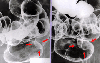

Rectal cartinoid tumor measuring 1.5 cm in size with invasion to the perirectal part and liver metastasis.

Tokyo Pref., Cooperative study between National Cancer Center and Kyushu Cancer Center

CT